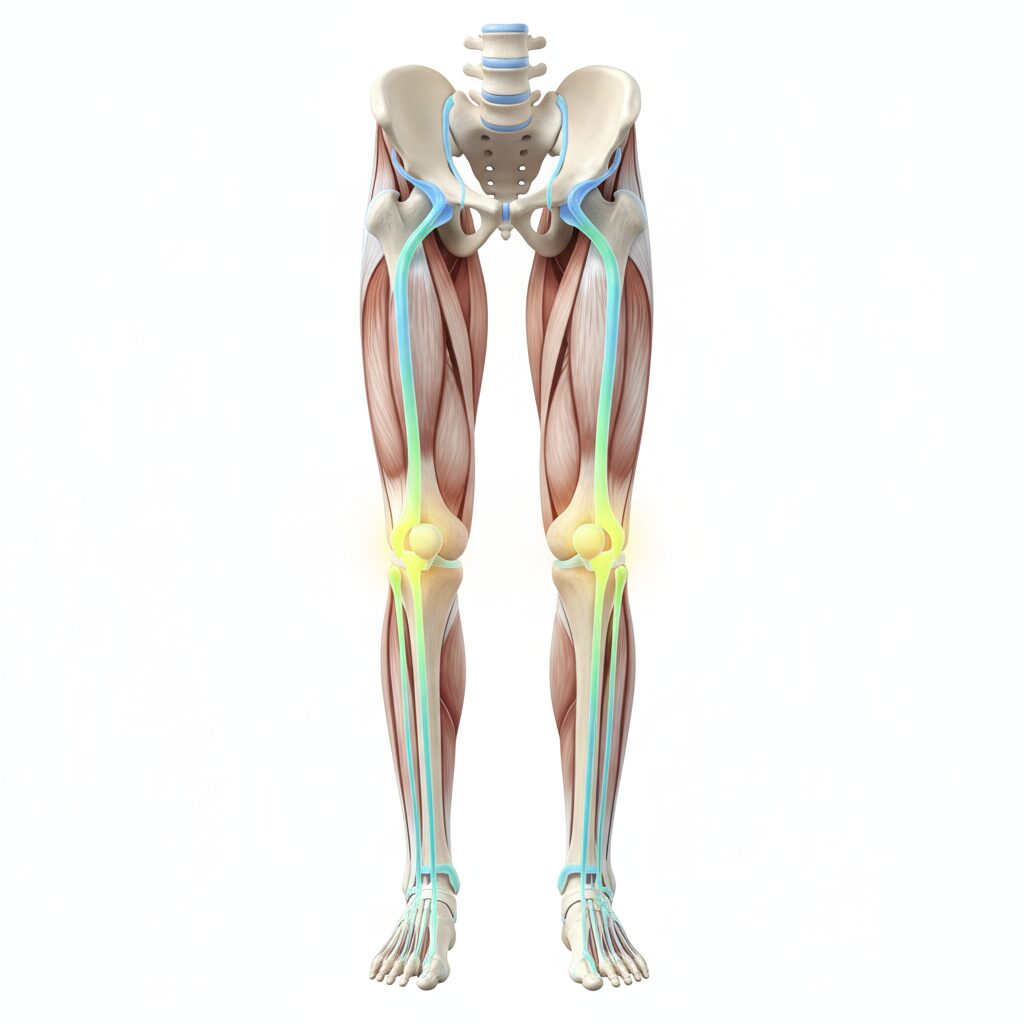

날씨가 추워지면 흔히 “무릎을 따뜻하게 해라”, “도가니탕을 먹어라” 같은 말씀을 많이 듣죠. 하지만 이런 방법만으로는 지긋지긋한 무릎 통증에서 벗어나기 힘든 게 사실이에요. 왜일까요? 무릎 통증의 진짜 원인은 무릎 그 자체가 아니라, 무릎 위아래에 있는 골반과 발목에 숨어 있는 경우가 많기 때문입니다.

많은 분이 모르시는 펙트 중 하나가 바로 **’발목 가동성’**입니다. 발목이 뻣뻣해서 위아래로 잘 움직이지 않으면, 우리가 걸을 때 발생하는 충격을 발목이 흡수하지 못하고 고스란히 무릎으로 전달합니다.

특히 겨울철에는 발목 근육이 더 굳기 마련인데요. 무릎을 만지기 전에 발목을 부드럽게 풀어주는 것만으로도 무릎에 가해지는 압력의 30% 이상을 줄일 수 있다는 사실, 놀랍지 않나요?

핵심 2. ‘내측광근’을 잡아야 무릎이 안 흔들려요

허벅지 근육이 중요하다는 말은 들어보셨을 거예요. 하지만 그중에서도 특히 **’내측광근’***에 집중해야 합니다. 무릎 바로 위 안쪽으로 볼록하게 튀어나온 근육인데요, 이 근육이 약해지면 무릎 뼈(슬개골)가 자꾸 밖으로 밀려 나면서 연골을 갉아먹게 됩니다.

소위 ‘X자 다리’처럼 무릎이 안으로 굽는 분들은 이 내측광근이 아주 약해져 있을 가능성이 커요. 이 근육만 탄탄하게 잡아줘도 무릎의 흔들림이 사라지고 통증이 눈에 띄게 줄어듭니다.

*주석: 내측광근 – 허벅지 안쪽에 위치한 근육으로, 무릎 뼈가 바른 궤도로 움직이게 잡아주는 ‘안전벨트’ 역할을 합니다.